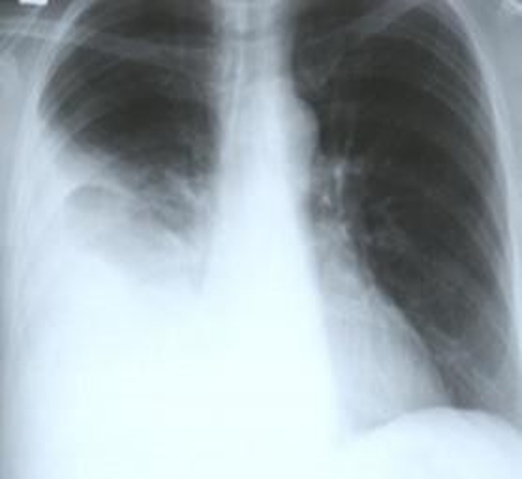

Routine investigations including complete hemogram, blood sugar, blood urea, s. creatinine, s. albumin, s. amylase, s .lipase, liver function tests and electrolytes, viral markers (HBsAg, Anti HCV) were within normal limits. Chest x-ray showed right sided pleural effusion (Figure 1). MRI of abdomen revealed huge cystic lesion measuring about 18cm×19cm×7cm, arising from right adnexal region with moderate ascites and moderate right sided pleural effusion (Figure 2, figure 3 and figure 4). Paracentesis was done. Ascitic fluid study revealed exudative fluid with protein 3.9 gm/dl. Gram stain and malignant cells in ascetic fluid were negative. ADA (adenosine deaminase) was normal of 8.68 U/L (normal <25>

Figure 1: Showing right sided pleural effusion